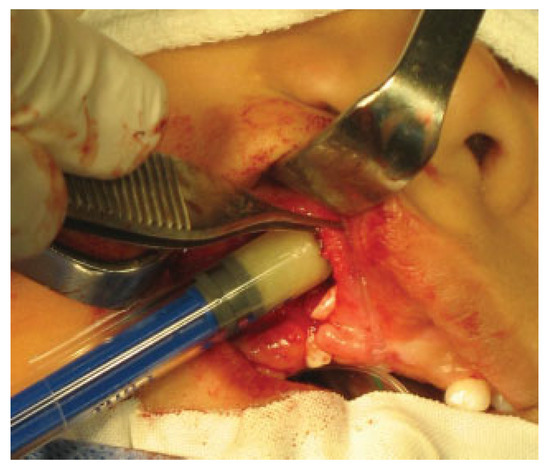

The putty or the iliac crest bone graft was taken and packed into the alveolar cleft between the cortical bone edges (►Figure 2) and then the lateral gingivoperiosteal flap is advanced to cover the cleft and is sutured to the smaller medial (anterior) flap and to the palatal flaps (►Figure 3). In patients with bilateral clefts, the same flap design was used. During the surgical procedure, a dose of cephazolin was administered and once the surgical procedure was finished, the patients were discharged with oral cephalexin for 7 days and liquid diet for 4 weeks.

Figure 3.

Closure of gingival mucoperiosteal flaps.